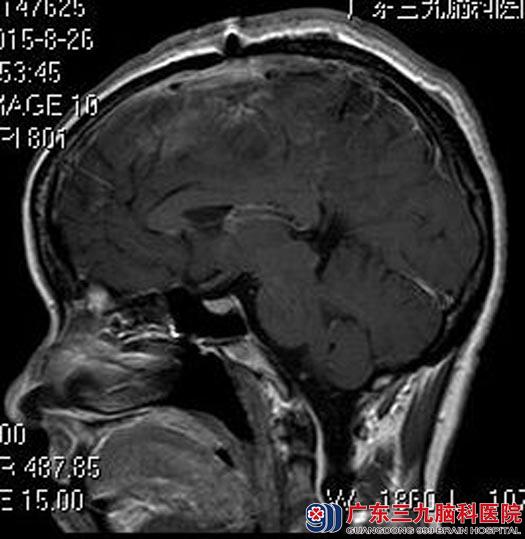

完善相关检查后,由综合神经外科鲁明主任主刀,在全麻下行左额镰窦旁脑膜瘤切除术,显微镜下见肿瘤部分呈灰白色胶状,部分质地中,血运一般,与脑组织边界较清,予以全切,肿瘤下极粗静脉完整保留,手术顺利。术后王医生无明显的功能障碍,康复出院。术后病理结果:脑膜皮细胞型脑膜瘤(WHO I级)。

▲手术后